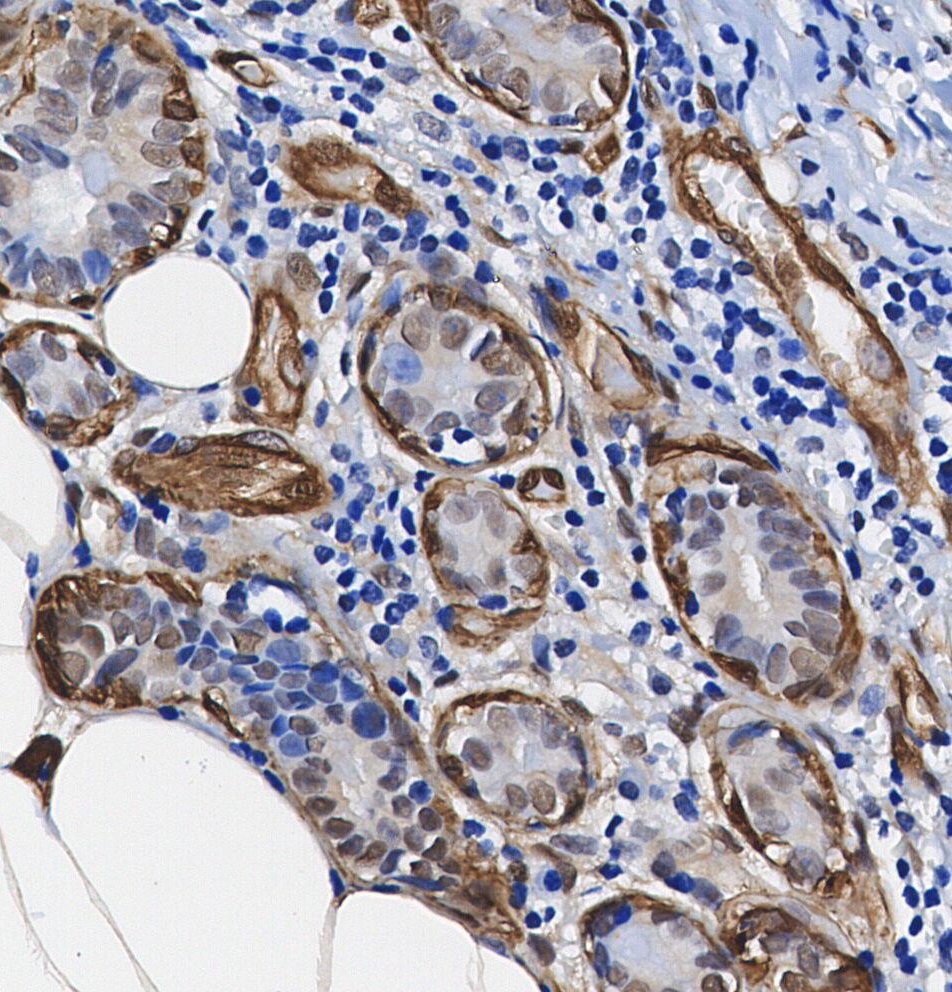

• Immunohistochemical analysis of formalin fixed paraffin embedded human Breast Cancer tissue with F1596 at 1/100 dilution.